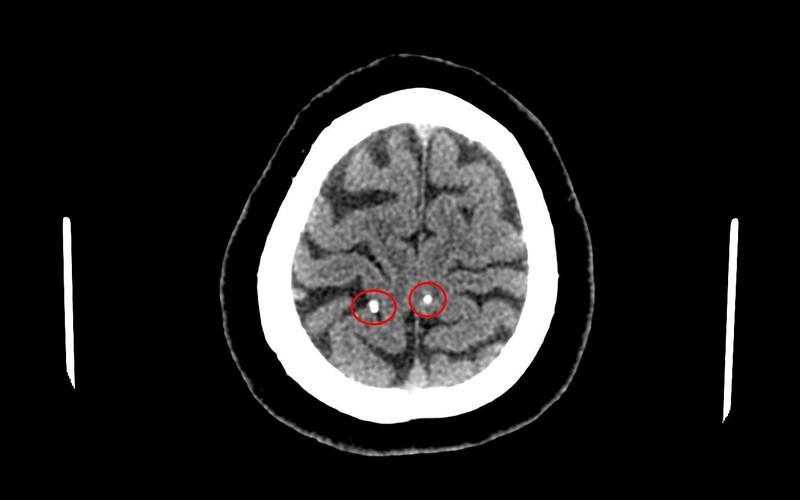

Qua thăm khám, chụp cắt lớp vi tính sọ não, các bác sĩ chuyên khoa Chẩn đoán hình ảnh kết luận trong sọ não người bệnh có hình ảnh nang ký sinh trùng (ấu trùng sán não - neurocysticercosis). Người bệnh cho biết trước đó có thói quen ăn đồ sống (gỏi cá).

Hình ảnh nang ký sinh trùng trong não người bệnh. |